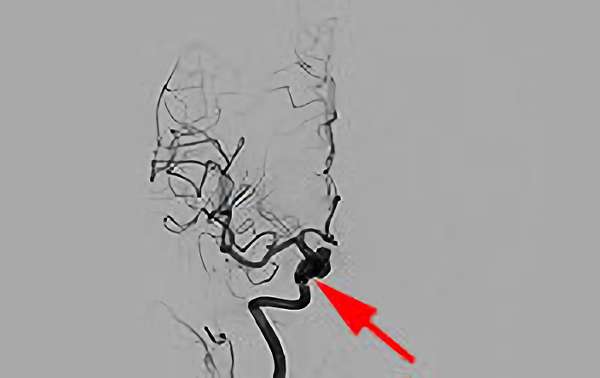

No.1627 手術前